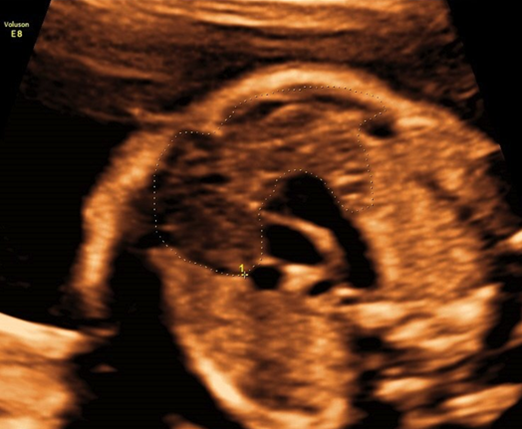

产科_胎心_三血管气管切面,胸腺可见